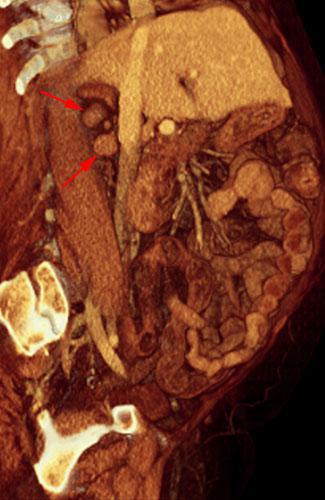

Recidiva adenopática de hipernefroma